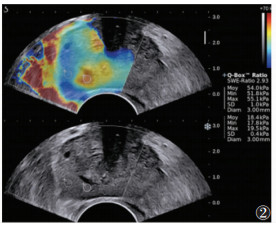

| 注:患者,男,57岁,PSA为26.62 μg/L,SWE图像上呈不对称分布,病灶处硬,Emax 55.1 kPa,Emean 54.0 kPa,Emin 51.8 kPa,病理证实为Gleason评分为7分的腺癌 图 2 前列腺癌的SWE图像 |